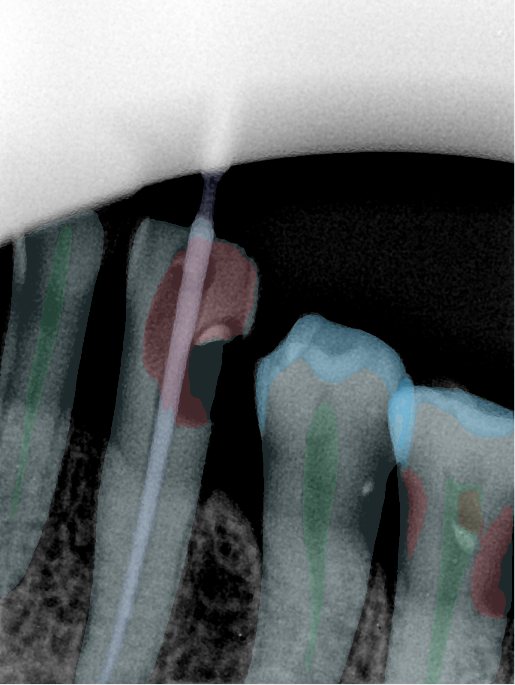

CR/DR 牙齿分割阶段记录

当前进展

- 完成了 CR/DR 牙齿相关分割训练

- 当前结果已经达到阶段预期,但仍有细节问题需要继续处理

相关测试

遇到的问题

- 训练过程中出现过 mask 下移问题

- 部分结果会出现 box 填充异常

- mask 边缘仍然有比较明显的锯齿感

第二版算法问题测试

| 第一版 | 第二版 | 是否解决 | |

|---|---|---|---|

![]() | ![]() ![]() 边角识别有问题 龋齿识别不全 牙髓识别不全 | ![]() | 解决 |

![]() | ![]() 边角识别有问题 识别信息有误 自查(牙冠识别不全) | ![]() | 解决 |

![]() | ![]() ![]() 边角识别有误 大范围填充识别遗漏 | ![]() | 解决 |

![]() | ![]() 识别信息不全 | ![]() | 解决 |

![]() | ![]() ![]() 边角问题 牙胶识别不全 牙冠识别不全 | ![]() | 解决 |

![]() 换图片 | ![]() | ![]() 牙冠部分稍微白了一些就识别成小范围修补,部分判断异常 | 部分解决,修复类略敏感,牙冠部分稍微白了一些就识别成小范围修补,部分判断异常。 |

![]() | ![]() ![]() 牙冠识别不全 牙髓不全 根尖炎龋齿识别有误 | ![]() | 解决 |

![]() | ![]() | ![]() | 解决 |

![]() 换图片 | ![]() | ![]() | 解决 |

![]() | ![]() 牙冠识别有误 | ![]() | 解决 |

![]() 换图片 | ![]() ![]() 边角识别有误 | ![]() 修复类敏感 | 部分解决,图像过白,导致修复类判断异常。 |

![]() 换图片 | ![]() 牙冠识别不全 | ![]() 修复类敏感 | 部分解决,图像过白,导致修复类判断异常 |

结论:修复类出现了不鲁棒的情况,后续需要加入轮廓的扩充数据进行增强。